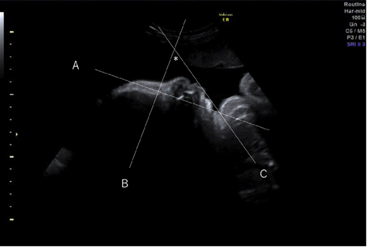

2D Radiography

More common method of detection.

Accompanied by genetic testing.

2D sonography show less details of the fetal features. The mandible angle and inferior facial angle indicated hypoplastic angle.

During 2nd Trimester – detection by ultrasonography